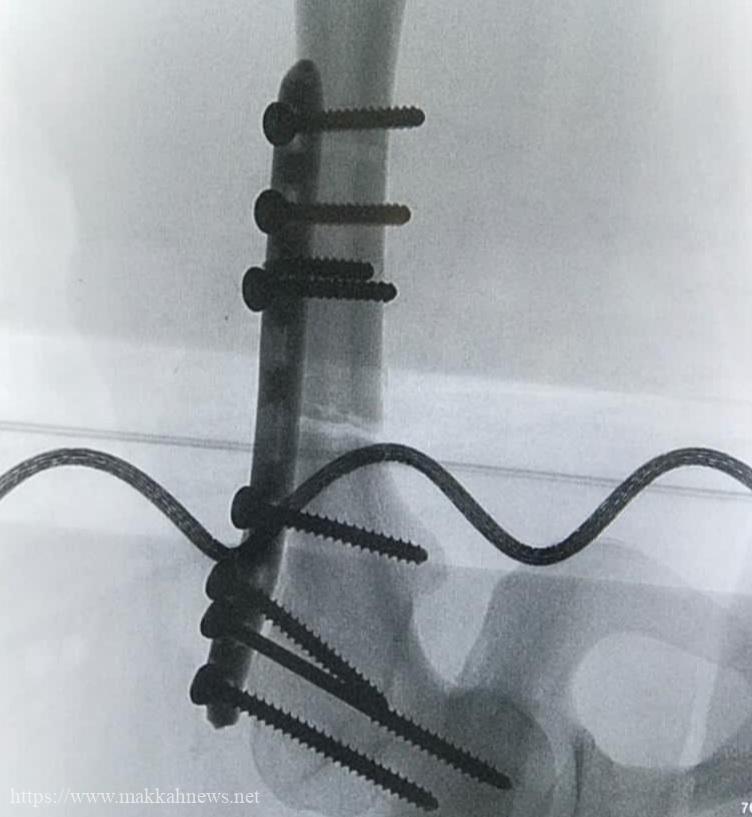

وكذلك تثبيت الكسور عند المصابين بإستخدام سيخ تيتانيوم نخاعي متشابك في حالة، واستخدام شريحة تيتانيوم متشابكة في الحالة الأخرى وذلك دون حدوث مضاعفات قبل أو بعد العملية وتم خروج المريضين وهما يتمتعان بتلاشي الألم ونطاق حركة وظيفي والتمكن من الحركة باستخدام وسائل مساعدة